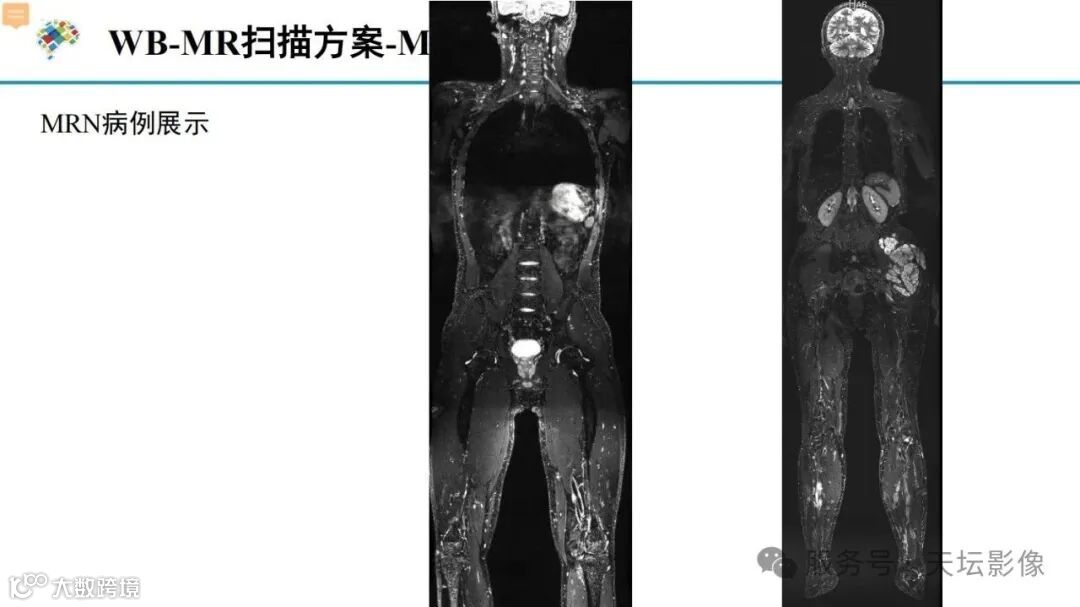

天坛扫描方案!NF1相关丛状神经纤维瘤推荐MR扫描方案